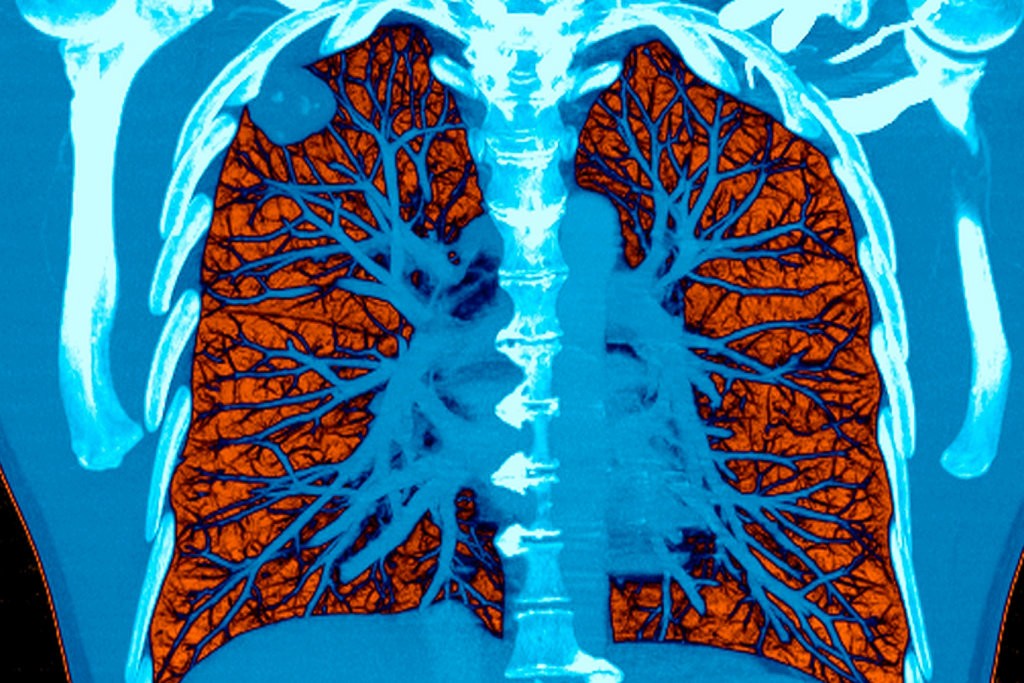

Các nhà khoa học của Google đã phát triển mô hình deep-learning và áp dụng với 2.763 bộ ảnh chụp CT chưa xác định được bệnh, do tổ chức Northwestern Medicine cung cấp, để kiểm tra độ chính xác của hệ thống mới của mình. Họ đã phát hiện hệ thống nhờ AI hỗ trợ này có thể phát hiện một số u phổi siêu nhỏ với mô hình AUC trong 0,94 trường hợp xét nghiệm. Các trường hợp này được lấy ra từ Kho Dữ liệu điện tử Tây Bắc, cũng như các nguồn dữ liệu khác của tổ chức Northwestern Medicine.

Hệ thống deep learning tối hưu hóa bản chụp CT quan trọng nhất và các bản chụp CT từ trước của bệnh nhân, coi đây là dữ liệu đầu vào. Các bản chụp CT từ trước có thể hữu ích trong việc dự báo ung thư phổi nguy cơ ác tính, vì tỷ lệ gia tăng các u phổi khả nghi có thể là chỉ số của u ác tính. Máy tính được lập trình để sử dụng các bản chụp LDCT chưa được khẳng định đầy đủ đối với bệnh nhân đã được khẳng định qua sinh thiết. Hệ thống mới cũng nhận dạng một vùng đáng quan tâm và xác định liệu vùng này có nguy cơ cao mắc ung thư phổi hay không.

Mô hình trên hiệu quả hơn 6 lần so với máy X quang trong trường hợp các hình ảnh chụp trước đó không thể xác định bệnh, và hiệu quả tương đương với các máy X quang khi đã có hình ảnh xác định được bệnh.